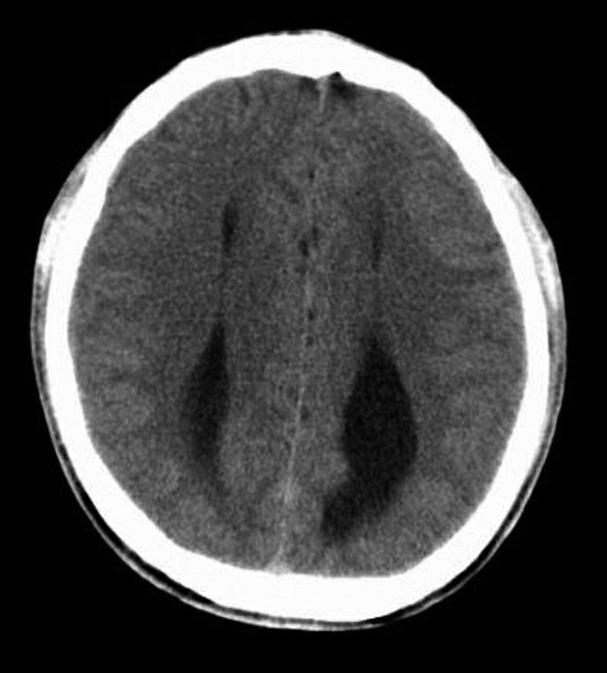

松果体、苍白球在成人期常出现钙化,属生理性钙化,一般无病理意义。需注意勿误诊为出血灶,尤其是单侧苍白球钙化时(图1-2-28)。

图1-2-28 苍白球生理性钙化

A.双侧苍白球对称性钙化,呈高密度影(箭);B.左侧苍白球钙化(箭),右侧苍白球钙化不明显